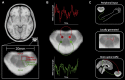

Even when we are at rest, our spinal cords show spontaneous, yet well organised, fluctuations of activity that might reflect sensory and motor networks.